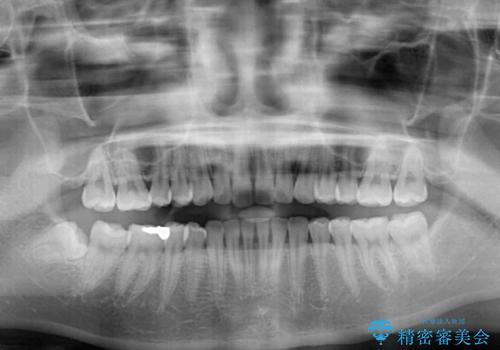

- 変色した前歯と突出した口元を気にして来院された患者様です。

口元の突出感はインビザラインにより歯列を整え、その後に、前歯をオーダーメイドタイプのオールセラミッククラウンにて補綴治療することとしました。